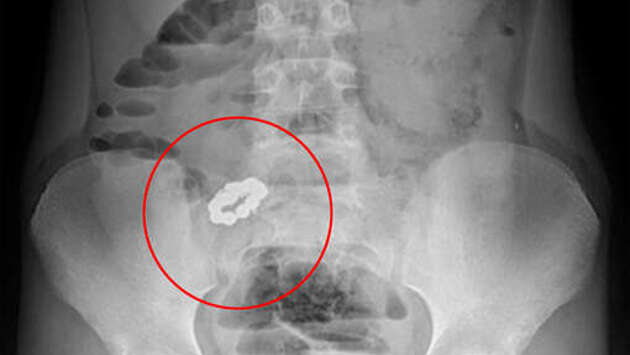

Хирурги Ивано-Матренинской больницы Иркутска спасли 12-летнего мальчика, который на спор проглотил несколько магнитов. Об этом сообщает пресс-служба медицинского учреждения. 12-летний школьник попал в больницу с подозрением на инородное тело в желудке. Выяснилось, что мальчик поспорил с друзьями и длительное время глотал магнитные шарики. Хирургам пришлось делать открытую операцию, чтобы извлечь инородные тела. "Инородные тела привели к множественным перфорациям тонкой кишки и развитию перитонита. После оперативного лечения у таких пациентов, кроме значительного рубца на брюшной стенке, имеется еще и риск формирования спаечной кишечной непроходимости, что может потребовать проведения повторных операций даже в отдаленные сроки", — отметили в больнице. Медики в очередной раз предупреждают родителей, что проглоченные магнитные шарики притягиваются друг к другу в организме и провоцируют образование пролежней на стенках кишечника, может развиться перитонит, требующий экстренного оперативного лечения.